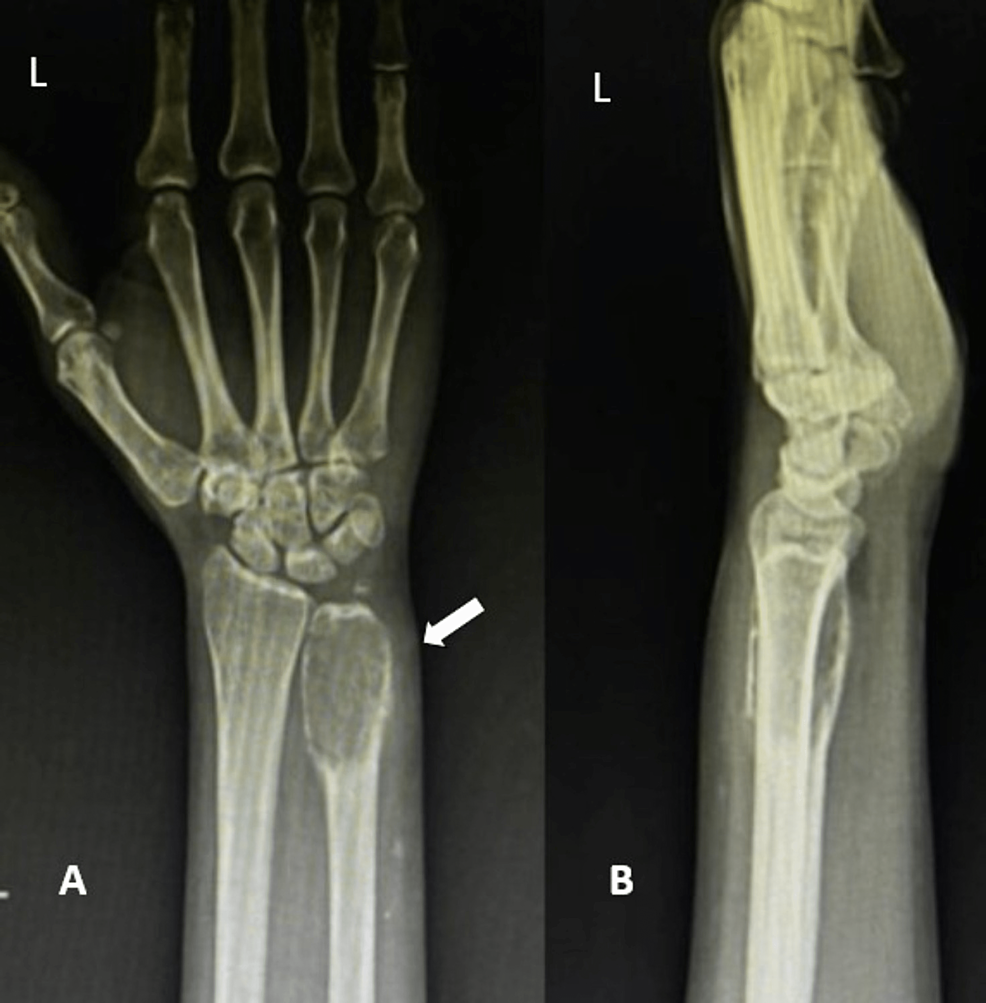

Mimics on Radiography of Giant Cell Tumor of Bone | AJR